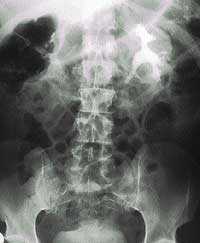

- Внутривенная урография. Рентгенологический метод обследования мочевыделительной системы. В вену вводится специальное контрастное вещество, затем через определенное время делаются серии рентгеновских снимков, на которых видно прохождение этого вещества через мочевыделительную систему. При этом оценивается функция почек, выявляются нарушения в строении мочевыводящих путей, камни в почках и другие заболевания органов мочевыделительной системы.